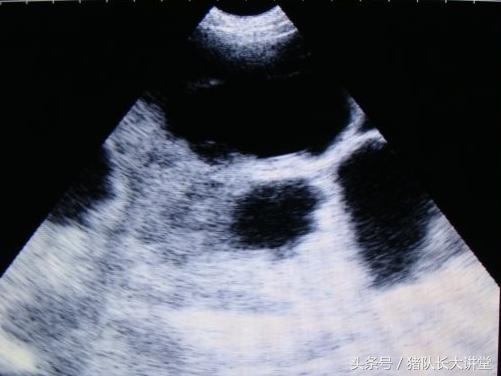

27天图

中间的黑球是初期胚胎